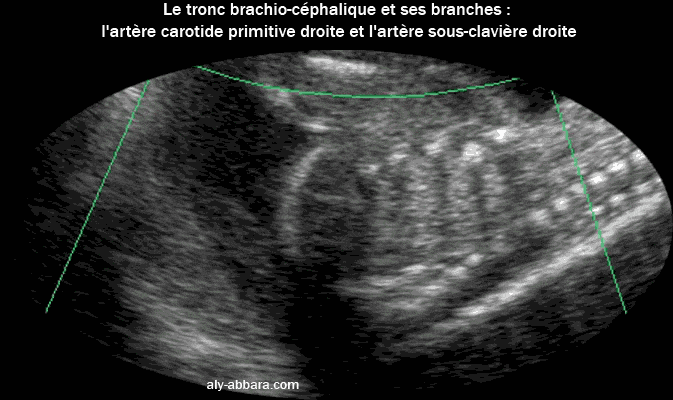

Image échographique avec Doppler en Dynamic flow montrant le tronc brachio-céphalique et ses deux branches, l'artère carotide commune (ou primitive) droite et l'artère sous clavière droite. |

| Le tronc brachio-céphalique est la première branche principale de l'aorte après sa naissance du ventricule gauche du cœur. |